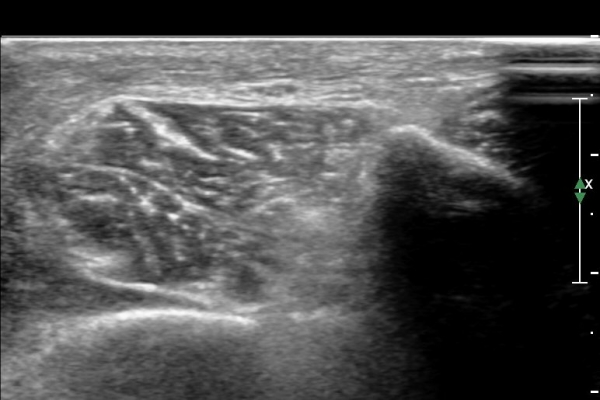

¾Æ·§´Ù¸® ¿ÜÃø Ⱦ´Ü¸é°Ë»ç¿¡¼ Àåºñ°ñ±Ù°ú ¹ß°¡¶ô½ÅÀü±Ù »çÀÌ¿¡¼ õºñ°ñ½Å°æÀÌ Á¤»óÀûÀ¸·Î °üÂûµÈ´Ù(»çÁø 1, , 2, 3, 4, 5).